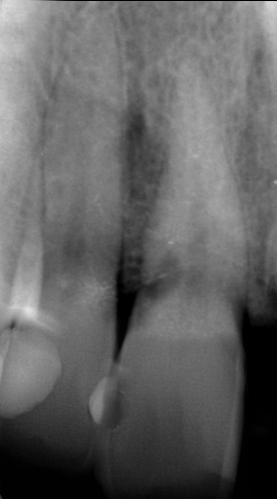

Ötvenes éveiben járó hölgyet fogorvosa irányította hozzánk a bal alsó 4-es fogának nagy méretű reszorpciójával [9. kép]. A hölgy ragaszkodott foga megmentéséhez, így a kezelés megtervezéséhez CBCT felvételt készítettünk a fogról [10. kép]. A felvételen a Patel-féle klasszifikáció szerinti Patel 3Ap reszorpciós elváltozás látható. A szájüregi vizsgálat során a fog bukkális felszínén gyulladt ínyt, mély parodontális tasakot és a fog nyaki részén, a foganyagon átsejlő reszorpciós lacunát találtunk [11. kép]. A fog szenzibilitás vizsgálat során nem reagált hideg ingerlésre. A pulpális érintettség miatt elvégeztük a fog trepanálását, majd lebenyt alakítottunk a kavitás láthatóvá tételéhez [12.

1. és 2. kép: Külső nyaki reszorpciós elváltozások CBCT képen.9. kép: Referáló orvos által készített röntgenfelvétel – 10. kép: CBCT felvételen 3 dimenzióban értékelhető a reszorpciós kavitás kiterjedése.

12. kép: Trepanálás és lebenyalakítás. – 13. kép: A gyulladásos szövet eltávolítása után a kavitás kiterjedése jól láthatóvá vált.